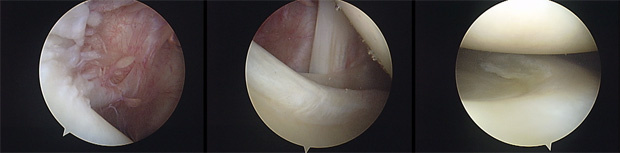

As microperfurações ou microfraturas buscam criar um revestimento fibrocartilaginoso em uma área restrita com ausência de cartilagem e exposição do osso subcondral. Sendo assim, a mosaicoplastia tem o objetivo de criar um revestimento com cartilagem hialina de área doadora do joelho para a cobertura do defeito condral.

Mostramos ao lado um caso de um paciente masculino de 33 anos com uma lesão osteocondral cística do côndilo femoral medial do joelho. O paciente apresentava dores de forte intensidade e derrames articulares de repetição.